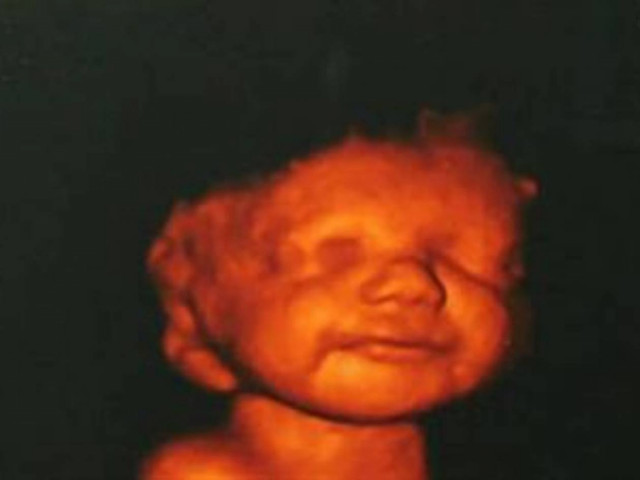

Aπίστευτο: Είδε το αγέννητο μωρό της να χαμογελά και δεν έκανε έκτρωση

WHAT THE FACT · 15.04.2013 - 13:58

O λόγος για την Katyia Rowe από την Βρετανία την οποία ενημέρωσαν οι γιατροί ότι το μωρό που κυοφορούσε..

Είδε το αγέννητο μωρό της να χαμογελά και δεν έκανε έκτρωση

ΚΟΣΜΟΣ · 15.01.2013 - 14:20

Το χαμόγελο του αγέννητου μωρού της, την έκανε να αλλάξει γνώμη.